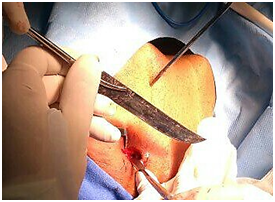

A male patient of 58 years old come to the emergency room after being attacked by other persons with a knife in the facial region. A physical exam shows a Glasgow of 15 points, with a cutting wound in the right side of the mouth, with oral opening limitation, pain in 6 of 10 points in VAE. Lateral and posterior-anterior x-rays were performed, showing the knife blade in horizontal position with an anterior-posterior direction and related with soft tissue located in the ascending mandibular branch in the right side to the cervical posterolateral región and adjacent to the mastoid process (Figure 1).

Figures 1 Lateral and posterolateral radiograph of the skull where the knife blade can be located.